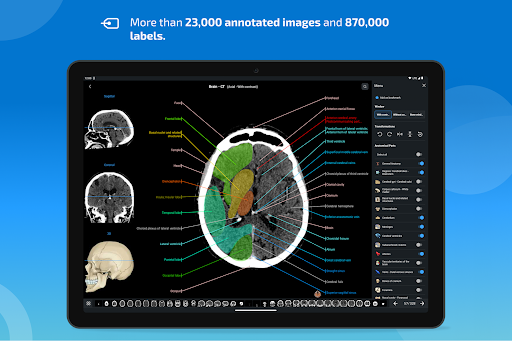

e-Anatomy tiene más de 26 000 imágenes que contienen series de imágenes en vistas axiales, coronales y sagitales, así como radiografías, angiografías, imágenes de disección, gráficos anatómicos e ilustraciones. Todas las imágenes médicas fueron etiquetadas cuidadosamente, más de 967 000 etiquetas disponibles en 12 idiomas, incluida la Terminologia Anatomica latina.

- Desplácese por los conjuntos de imágenes arrastrando el dedo

- Acerque y aleje el zoom

- Toque las etiquetas para mostrar las estructuras anatómicas